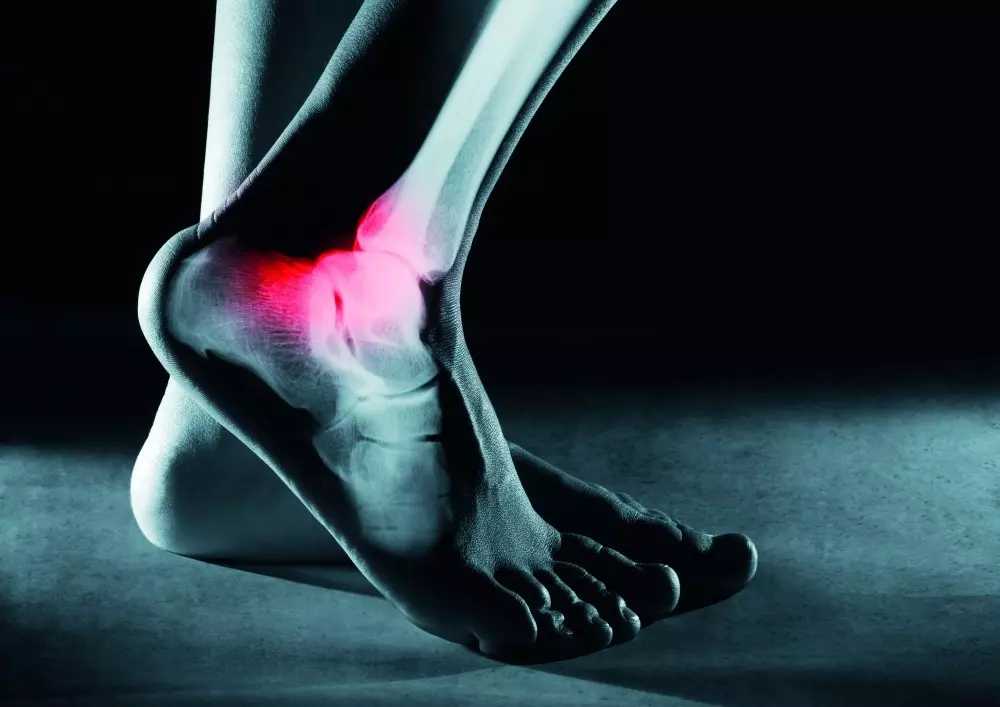

W dziale „Z praktyki gabinetu” prezentujemy, jak krioterapia miejscowa sprawdza się w rehabilitacji stopy. Zespół ekspertów wskazuje, że zimno jest najlepszym środkiem przeciwzapalnym we współczesnej fizykoterapii. W opracowaniu znajduje się opis krioterapii miejscowej, wskazania i przeciwwskazania do terapii oraz możliwość zastosowania jej w sporcie czy po operacjach. Będą mogli zapoznać się Państwo także z opisami kilku przypadków po przebytych urazach stóp.